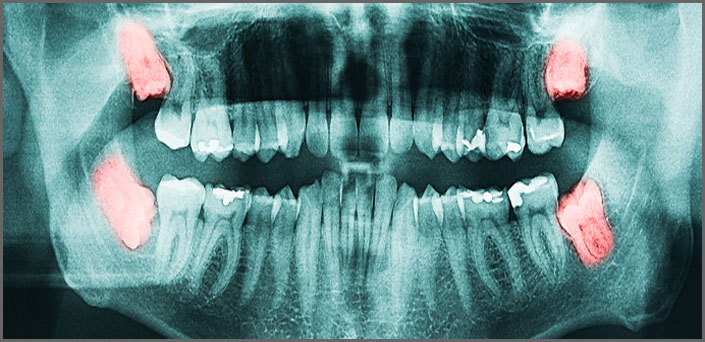

Surgical extractions concerns the removal of the entire or part of a tooth, for which the removal requires a small incision in the gum and the removal of alveolar bone.

These teeth are usually covered or partially covered wisdom teeth, the roots of milk teeth that are wrapped around the permanent teeth and blocks thier direction, broken roots and root tips, tooth deformaties and teeth with very curved roots and teeth that sink back below the occlusal plane etc.